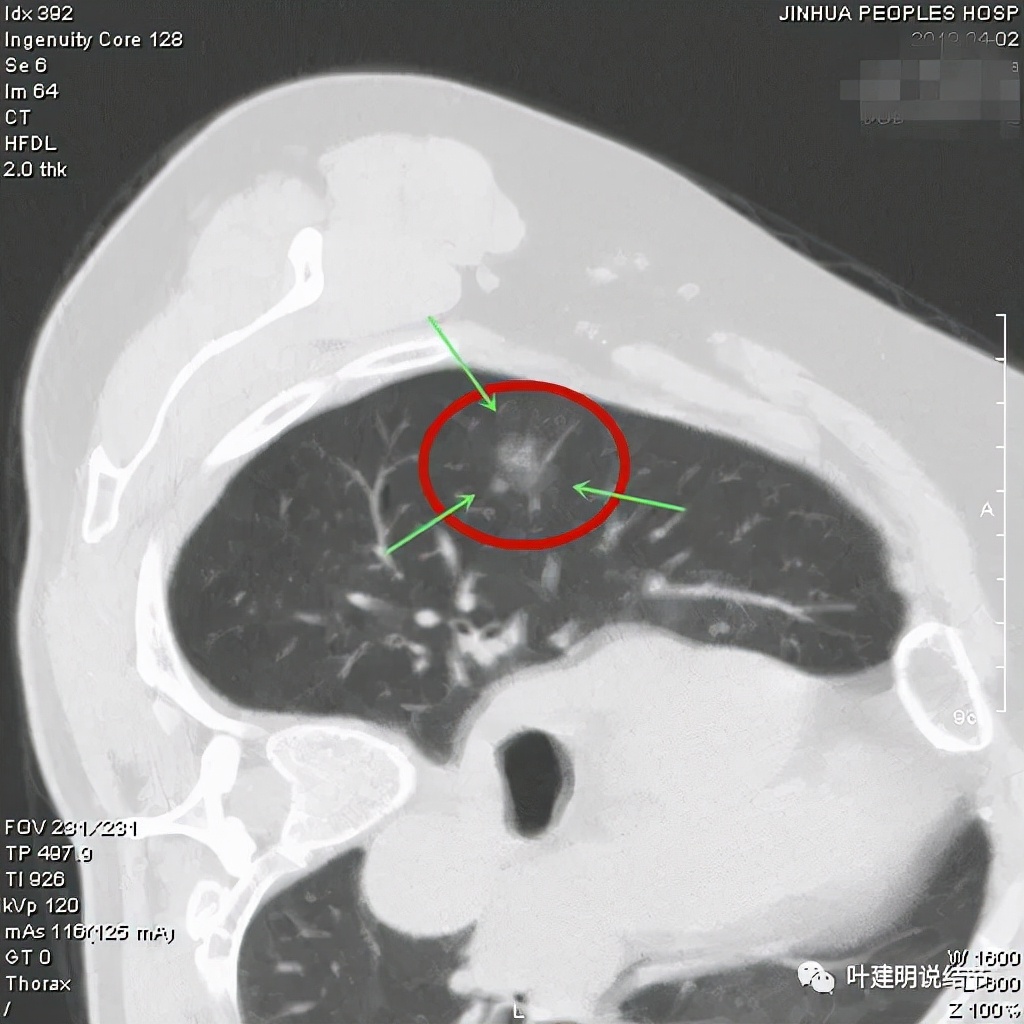

上图非常不舒服,病灶边缘有毛刺(蓝色箭头),中间有偏实性成分(粉色箭头所指),整体看密度不均杂乱

上图示明显的血管进入(桔色箭头),而且进入病灶后散大模糊,不是穿行;病灶内有高密度区域(粉色箭头)。但事后分析,绿色箭头所指的磨玻璃部分密度仍是过低,且边缘显模糊,与浸润性腺癌可能不是太符合。

以上三图均示典型的混合磨玻璃,实性成分杂乱,整体密度杂乱,并有血管征,是较为典型的浸润性腺癌影像表现。

看了后处理重建的图像,我们认为基本上应该就是浸润性腺癌了,从平扫到靶扫到靶扫描后处理,一步一步往更恶性的角度考虑。某A按我们的建议进行了单孔胸腔镜下手术,结果术中快速病理切片示:原位腺癌。我还觉得术后病理会不会升级,所以还在等石蜡切片,因为影像上,特别是后处理重建的图像太像浸润性腺癌了,结果仍是原位腺癌: